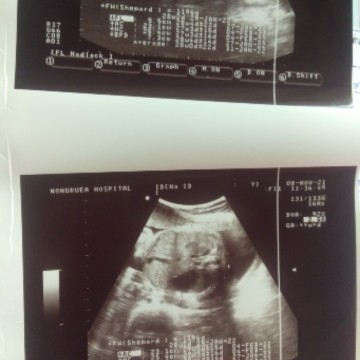

ตั้งครรภ์28+1สัปดาห์ นน.1196gตกเกณฑ์มั้ยคะ

อายุครรภ์28+1หมอว่าท้องเล็กแต่น้อง นน.1196gถือว่า นน.น้องตามเกณฑ์หรือน้อยกว่าเกณฑ์คะแม่ๆ